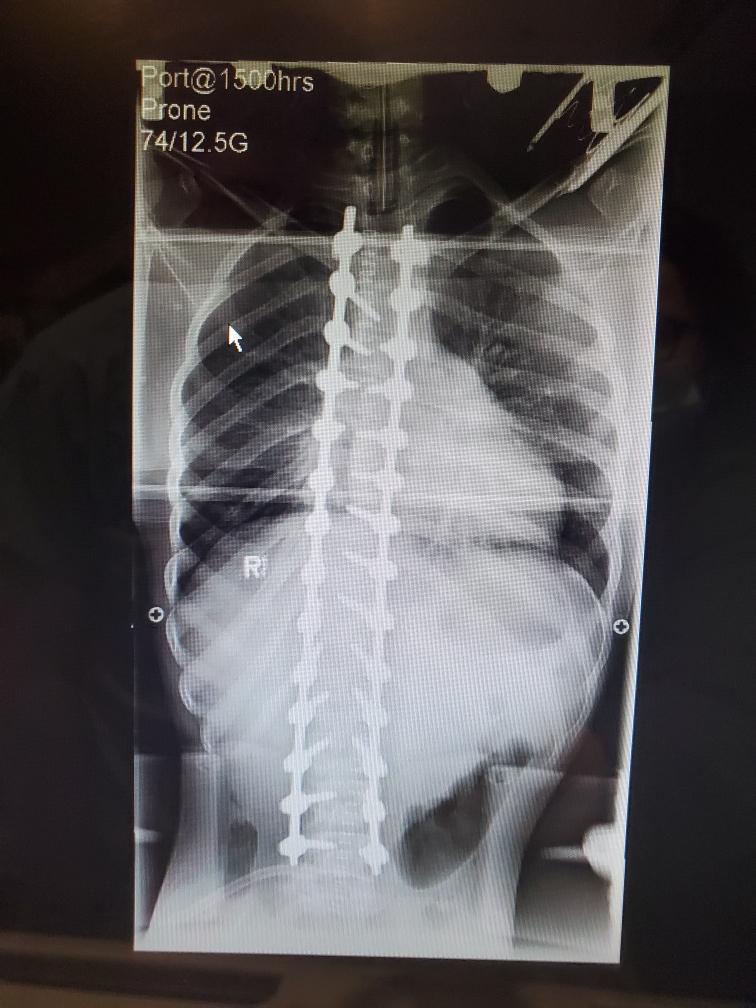

The Gallant family from Fort St. John has been trying to get their son Devin surgery to correct a worsening curve in his spine.

Devin has Type-3 Spinal Muscular Atrophy (SMA), a genetic disease that causes the body’s muscles to waste away.

But one day before Devin’s 15th birthday, he underwent surgery at B.C. Children’s Hospital and has already been discharged from the ICU.